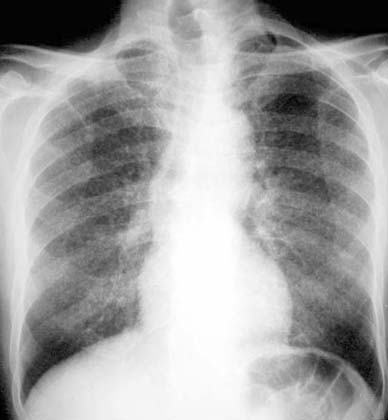

Miliary Tuberculosis

Bilateral diffuse <5mm nodules. Click on the image to see close up.